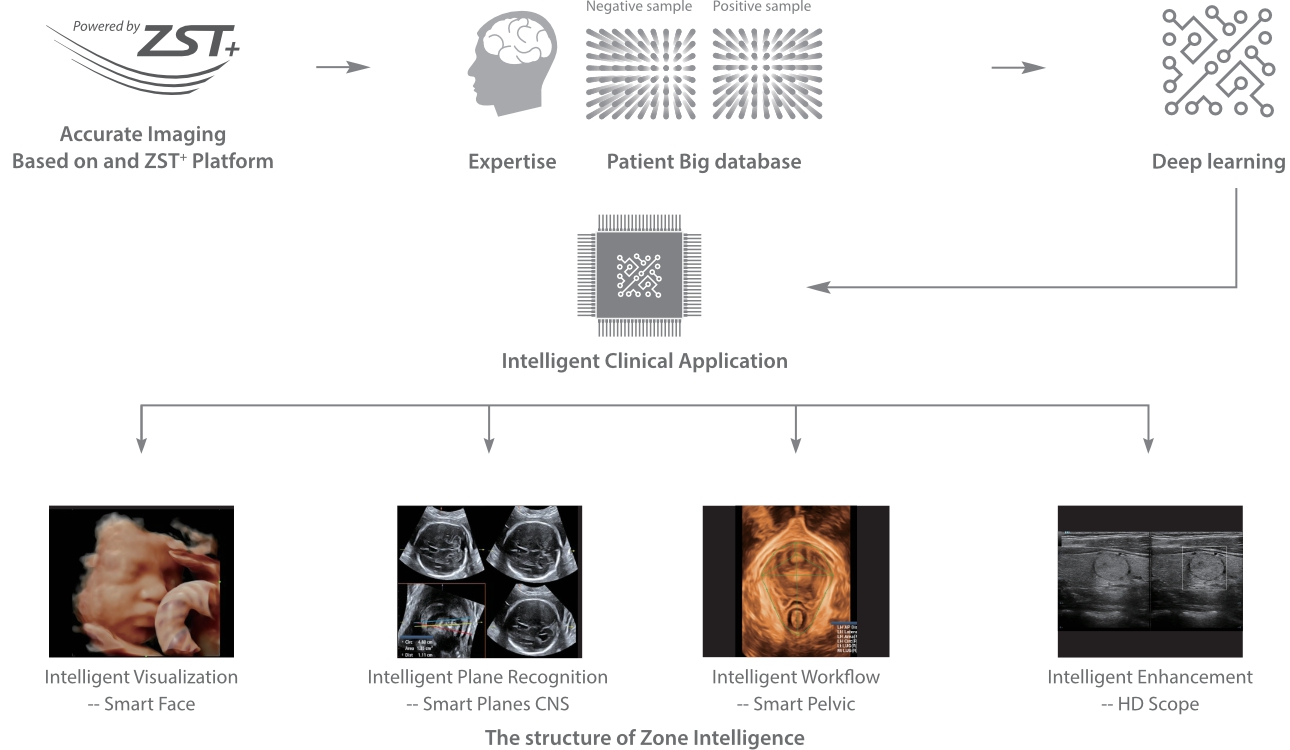

Desde que a empresa foi fundada, a Mindray est├Ī continuamente explorando novas maneiras de melhorar a confian?a no diagn├│stico. Alimentada pela mais revolucion├Īria tecnologia ZONE Sonography?, a nova plataforma Resona 7's ZST+ traz uma qualidade de imagem ultra-som a um n├Łvel superior por aquisi??o de zona e processamento de dados do canal.

Assim como o n├Łvel de qualidade de imagem premium, o Resona 7 tamb├®m melhora as capacidades de investiga??o cl├Łnica com o revolucion├Īrio Fluxo V para avalia??o hemodin?mica vascular e a aquisi??o de plano mais inteligente do conjunto de dados 3D para diagn├│stico CNS fetal. Combinando a opera??o mais intuitiva baseada em gesto de multi-toques e todos os recursos cl├Łnicos essenciais, Resona 7 est├Ī realmente conduzindo novas ondas na inova??o de ultra-som.